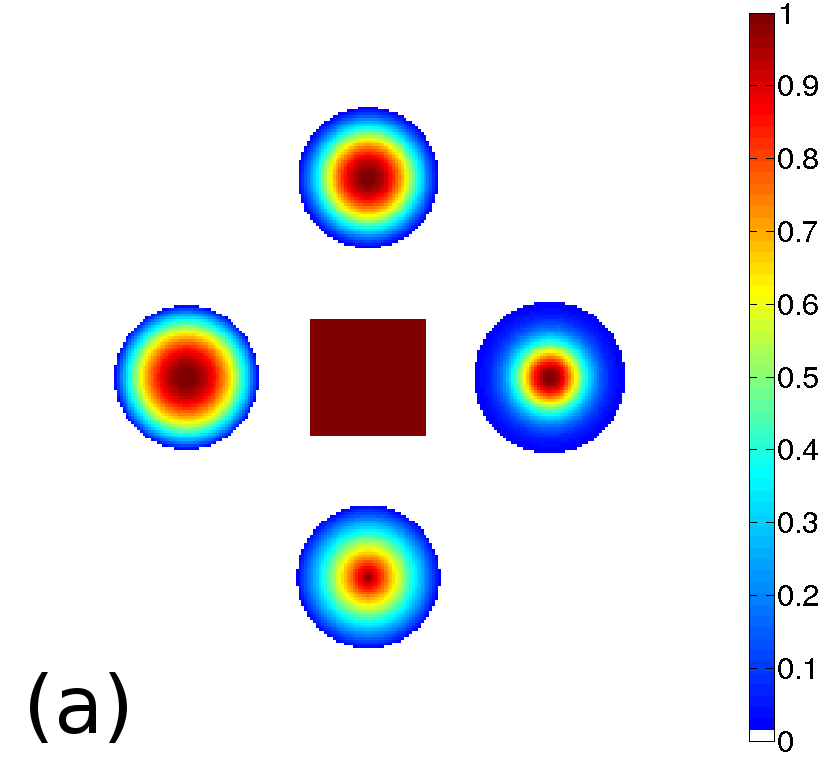

To test the proposed penalty in regularized tomographic reconstruction we designed an analytical phantom which consists of a smooth (two Gaussians and two parabolas) and piecewise-constant (one rectangle) functions (see Fig. 1).

To avoid of reconstructing on the same grid where projection data was generated (so-called reconstruction with “inverse crime” [16]), we used a higher resolution of the phantom on a isotropic pixel grid to generate projections with a strip kernel [1]. Then Poisson distributed noise was applied to the projection data, assuming an incoming beam intensity of 3 (photon count). Reconstructions were calculated on a isotropic pixel grid and with a linear projection model [1]. We used 90 projection angles in 180 degrees (assuming a parallel beam geometry) to reconstruct the phantom.

Reconstructed images are presented in Fig. 4. Since CGLS-TV- reconstruction might look more appealing than CGLS-EL we also show the surface representations of reconstructed images (see Fig. 5) and horizontal middle cross-sections (see Fig. 6).

One can notice that CGLS reconstruction is very noisy. CGLS-TV method better suppresses noise, however smooth features are strongly affected by the “staircasing” effect. CGLS-TV- method provides reconstruction with smoother features and CGLS-EL method resolves smooth features even better (e.g. cone-shaped parabola). Although CGLS-EL method performs very well for smooth objects one can notice the wave-like variations of intensity in the background and also at the top of the rectangle (see Fig. 6). This issue can be explained by the properties of our regularizer, in contrast to TV, our penalty does not seek the sparsest solution and does not penalize strongly (pushing to the constant value) a small intensity perturbations. The EL term tends to preserve all sharp edges while uniform noise is smoothed isotropically with the Laplacian. In Fig. 6 one can see that the CGLS-EL method provides better recovery of smooth features while slightly higher (compare to TV and TV-) perturbations visible in uniform areas (the top of the rectangle), however, the edges of the rectangle are defined sharper with the EL penalty.